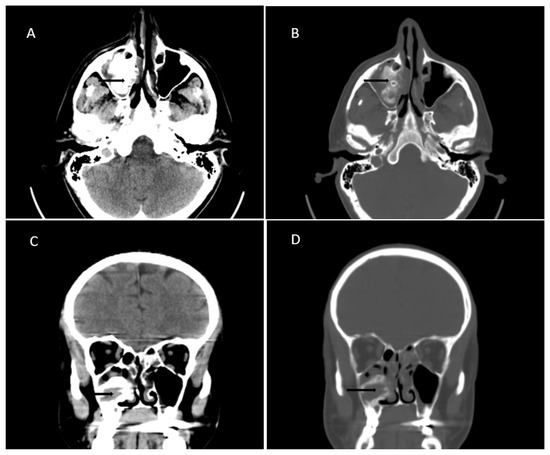

2. Case Presentation

3.2. Diagnosis and Radiological Features